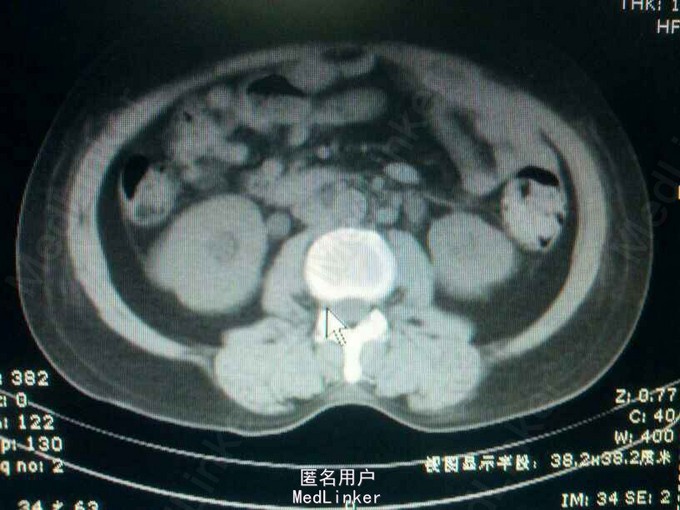

55岁,女性,宫颈癌放疗后两年,阴道出血半年,少尿20天

双肾区叩痛(+-),耻骨上区皮肤增厚,无明显压痛!会阴及双下肢水肿明显! 辅助检查:ct:双肾轻度积水,双侧输尿管全程扩张。膀胱充盈,伴大量血凝块!宫颈癌复发!肾功:血肌酐988,钾5.4,

宫颈癌复发侵犯膀胱及双侧输尿管下段。 肾功能衰竭尿毒症期 膀胱内血凝块